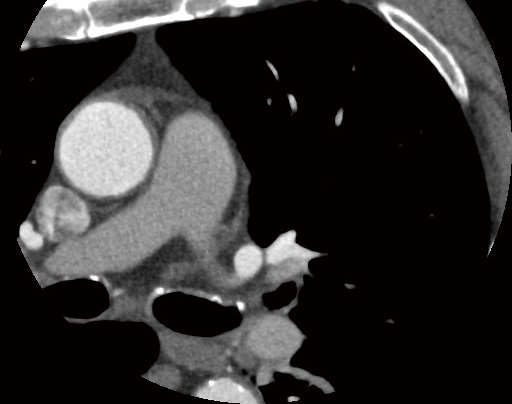

a:Aquilion ONE / PRISM N-UX Edition

同一患者の冠動脈CT a SD:16.7 同一患者の冠動脈CT a DLP:228.5mGy・cm

b:Aquilion PRIME

同一患者の冠動脈CT b SD:25.3 同一患者の冠動脈CT b DLP:406.7 mGy・cm

図1 同一患者の冠動脈CT

80列のAquilion PRIME(b)との比較。80列でも高ピッチで被ばく線量は少なめだが、Aquilion ONE / PRISM N-UX Edition(a)では画質を担保しつつ被ばく線量が半分近く低減されている。